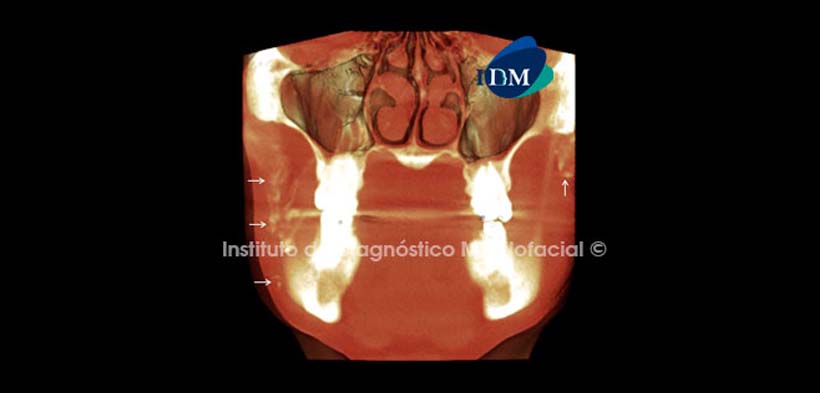

Así mismo, el software Romexis nos brinda diferentes opciones de reconstrucción 3D, como por ejemplo la opción para evaluar los tejidos blandos en la cual observamos las calcificaciones con un aspecto más difuso y confirmamos su disposición cefálico-caudal antes descrita (Fig. 3 y 4).